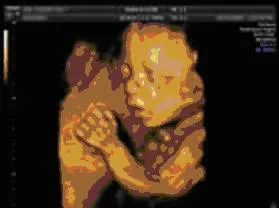

主に、表在領域と整形外科領域が検査対象となります。表在領域では、甲状腺や耳下腺、顎下線、舌下腺などを始め、皮下腫瘤、リンパ節などの観察をしていきます。整形外科領域では、関節や腱、軟骨、筋肉など疾患や関節リウマチなど、各種疾患の診断に役立ちます。 - 胎児4D超音波検査

3Dとは長さ・幅・奥行きの情報を合わせて立体的な画像にしたものです。4Dとは3Dにさらに時間という情報を加えたものです、胎児4D検査ではリアルタイムでお腹の赤ちゃんの様子を観察することができます。条件によっては、赤ちゃんの指を加えた様子や、顔の表情などが詳細に確認できます。検査は妊娠25週前後が最も適しています。検査後は、赤ちゃんの様子を撮影したDVDをお渡ししています。